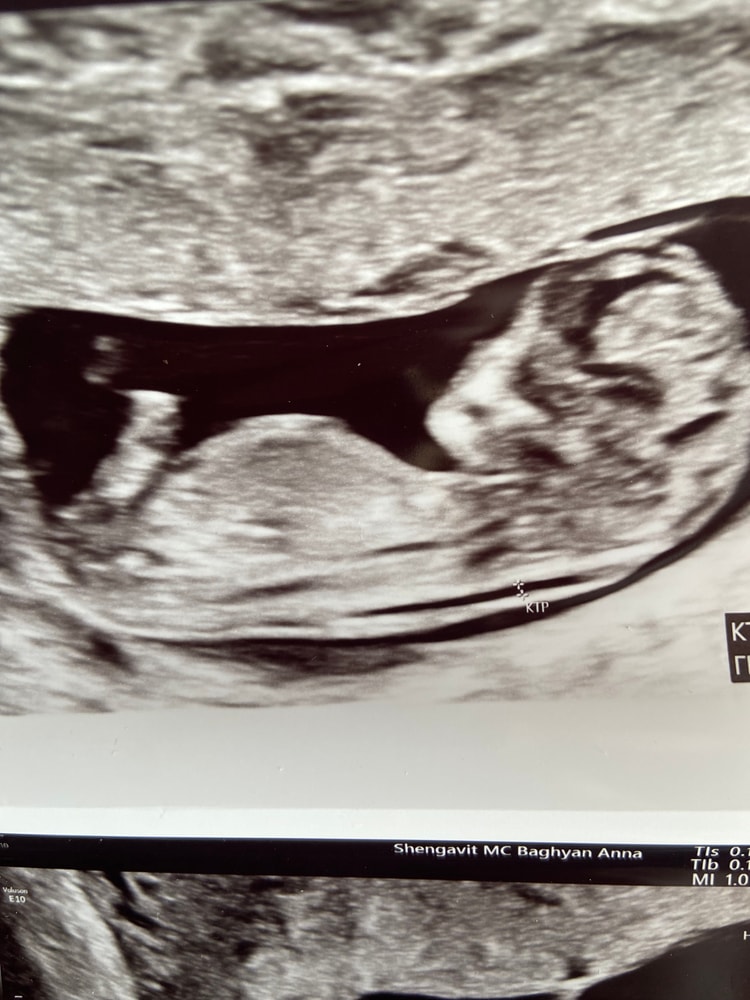

Здравствуйте, после первой беременности прошло ровно 6 лет и вот наконец получилось долгожданная вторая беременность. Конечно же первым желанием было чтобы малыш был здоровым, но первый у меня богатырь, хотелось принцесску🫣.Настала 12 неделя и на скрининге сказали что по строению малыша-мальчик но полового бугарка еще не было видно. Если есть кто то кто по фото узи может что то сказать буду очень благодарна🥰🥰